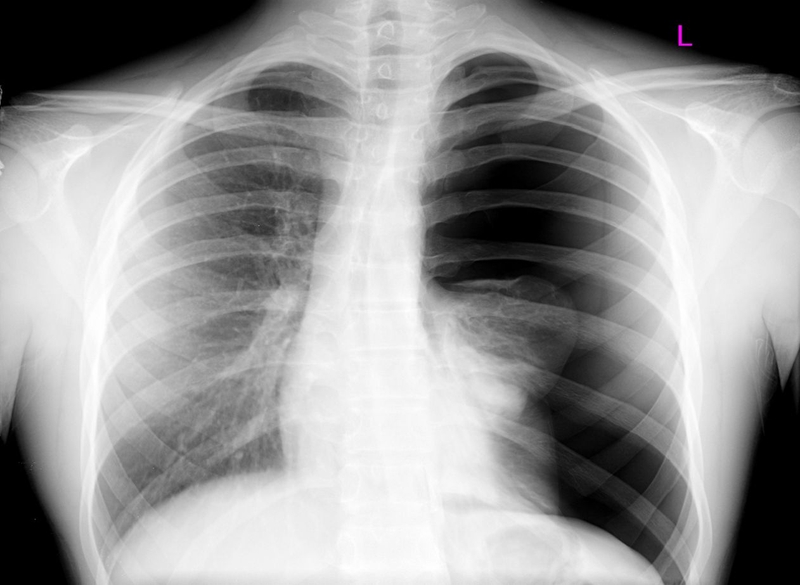

Đây là tình trạng không khí tích tụ trong khoang màng phổi. Nguyên nhân gây ra tràn khí màng phổi áp lực có thể do tự phát hoặc thứ phát bệnh lý phổi như chấn thương, xơ nang, hen suyễn, viêm phổi,...

Lượng không khí tích tụ nhiều theo hiệu ứng van một chiều mà không thoát được ra ngoài đến một mức độ nhất định sẽ gây áp lực lên tim và các mạch máu khác. Cuối cùng, khi áp suất tăng cao, hoạt động bơm máu của tim đến các cơ quan bị hạn chế do mạch bị ép chặt.